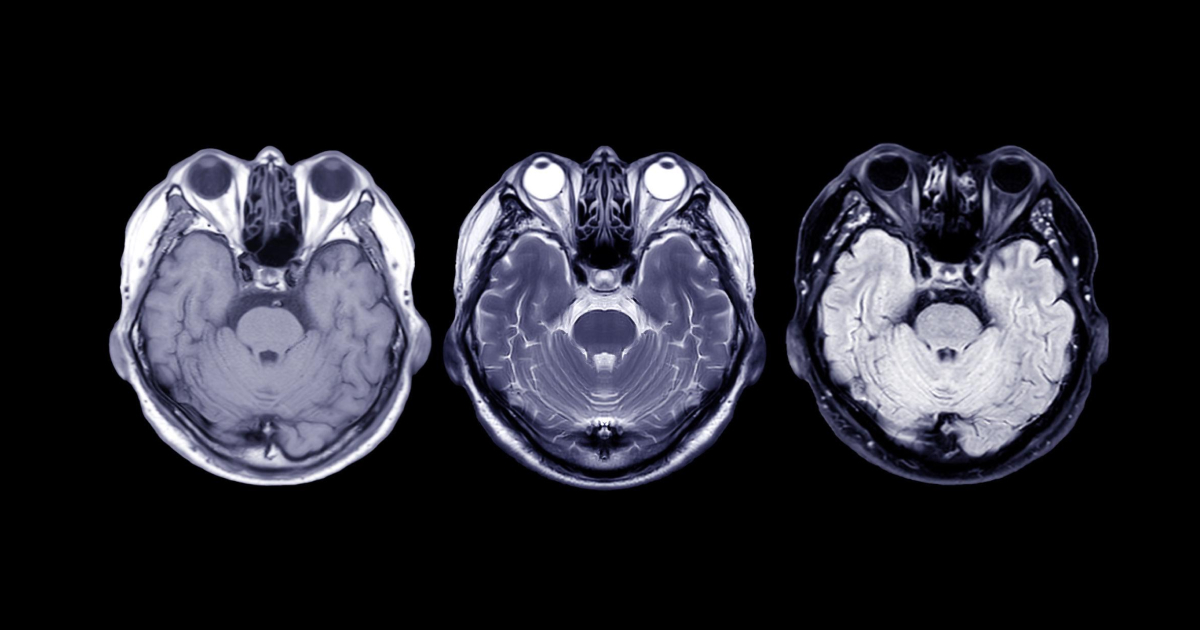

Як МРТ «бачить» тканини організму

МРТ працює за принципом взаємодії магнітного поля та радіохвиль з атомами водню в тканинах. Різні тканини — м’язи, жир, рідина, кістки — по-різному реагують на ці сигнали. У результаті на зображенні формується контраст між структурами.

На томограмі це виглядає як різні відтінки сірого — від дуже темних до майже білих ділянок. Саме цю різницю радіолог і описує термінами інтенсивності сигналу.